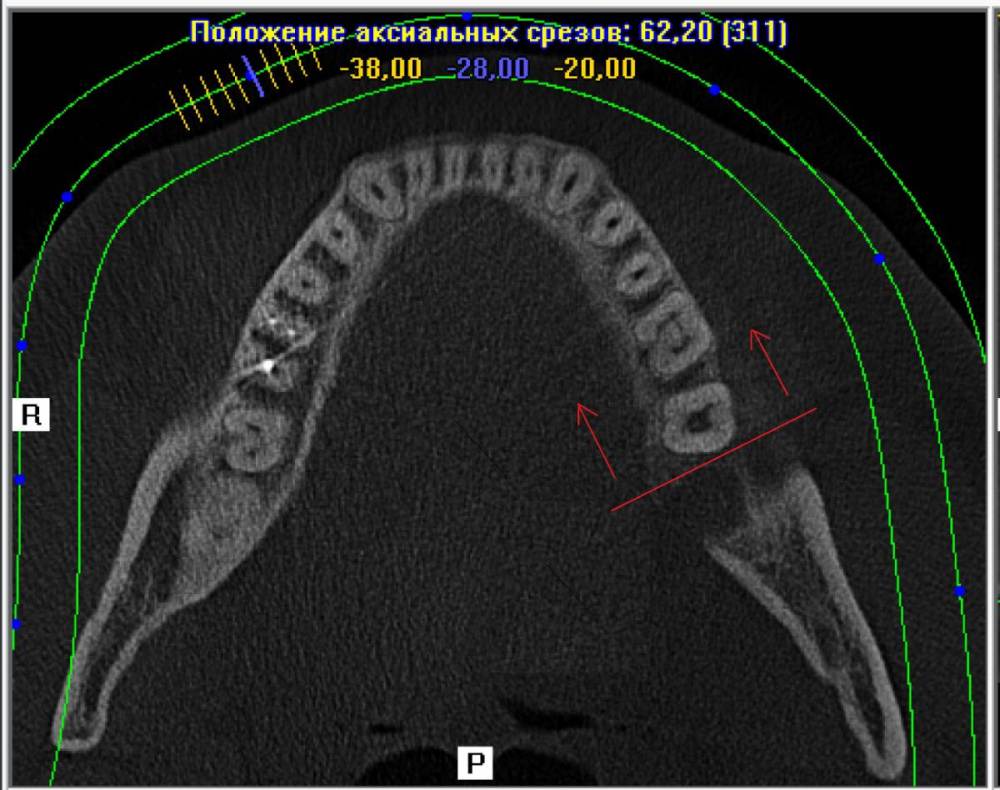

ЕвгенийЗ Опубликовано 24 июня, 2021 Автор Поделиться Опубликовано 24 июня, 2021 Плоскость чуть ниже нижней десны Ссылка на комментарий

ЕвгенийЗ Опубликовано 24 июня, 2021 Автор Поделиться Опубликовано 24 июня, 2021 И если немного выше поднять плоскость, то как раз виден этот край альвеоллы(или как правильно?). Но он вроде как отколат что ли? Не могли бы взглянуть пожалуйста. Там где стрелочка, походу этот край и вылез. И еще плоскость по зубному ряду Ссылка на комментарий

ЕвгенийЗ Опубликовано 24 июня, 2021 Автор Поделиться Опубликовано 24 июня, 2021 Дополнение к последнему фото. Это вот эта плоскость Ссылка на комментарий

АнтонТЛТ Опубликовано 24 июня, 2021 Поделиться Опубликовано 24 июня, 2021 Да, это этот край альвеолы 1 Ссылка на комментарий